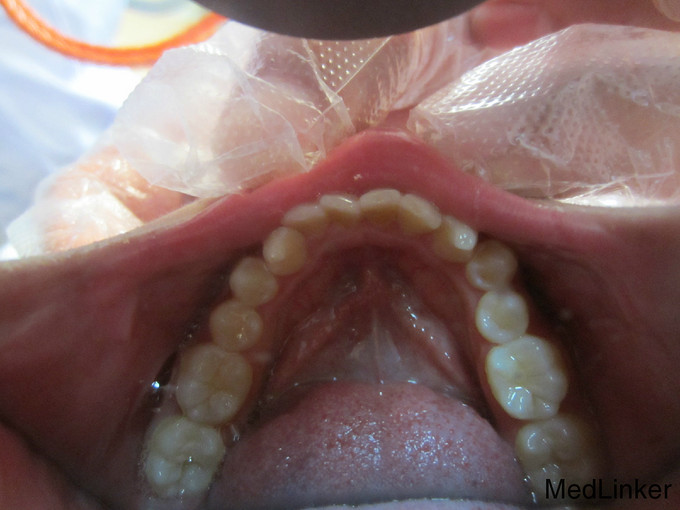

检 查:双侧颞下颌关节开口弹响,开口度一度; 模型测量分析:3度深覆合,上下颌轻度拥挤,spee曲线陡峭,上下颌尖牙尖锐、宽度较小,; 头 颅 侧位片:下颌平面角低角,下颌后缩,余正常; 辅 查:曲面断层片、头颅侧位片,双侧颞下颌关节片

诊断:深覆合、下颌后缩导致颞下颌关节负担加重,引起关节紊乱 治疗:一期:制作合平面导板,戴用一月后关节症状减轻,确定病因; 二期:带用固定矫治器,首先排齐上颌4个月,之后配合平面导板及摇椅弓排齐整平下颌5个月,调整上下颌咬合关系3个月,精细调整2个月,保 持1个月后拆除矫治器,患者自觉关节症状明显好转,制作保持器保持。

三个月后复查,颞下颌关节无不适,保持效果较好,交待注意事项,继续保持